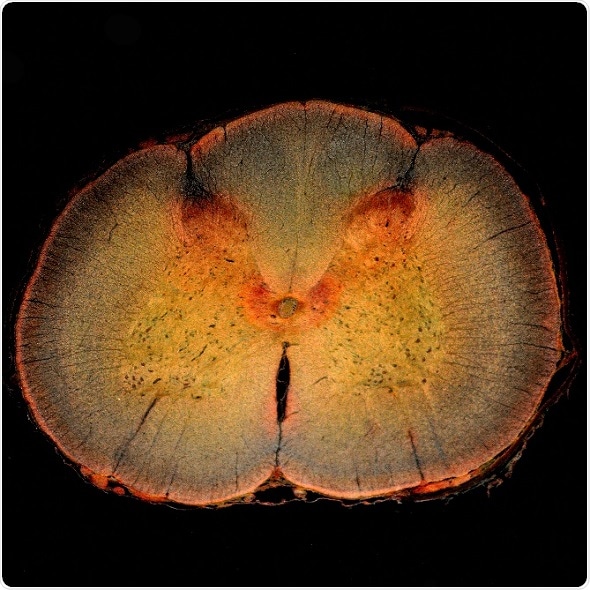

Spinal cord cross section, including the spinal cord dorsal horn, where pain is processed.

Credit: dw_ross/Flickr.

The mechanisms underlying both normal and neuropathic pain rhythms have been unclear. To gain new insights, Crodelle and colleagues built a mathematical model that simulates how pain is transmitted from a nerve to the spinal cord’s dorsal horn, where pain is initially processed.